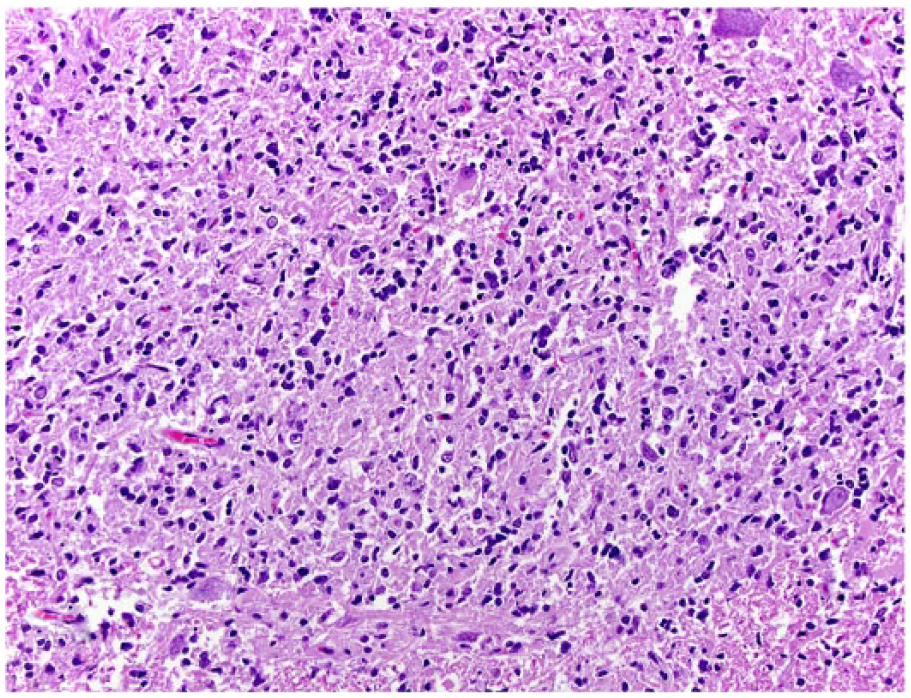

Histologically, all tumors were poorly demarcated, often infiltrative, and affected mainly the spinal gray matter. Oligodendrogliomas (cases 1, 3, 6, and 7) were poorly demarcated and affected primarily the gray matter, but also extended into the adjacent white matter (Fig. 2). Neoplastic cells were arranged in sheets or cords supported by preexisting parenchyma or a fine fibrovascular stroma with occasional microvascular clusters (glomeruloid vessels; cases 3 and 6). Neoplastic cells were mildly to moderately pleomorphic and had a moderate amount of cytoplasm, with distinct borders, that was either clear (forming a perinuclear halo) or contained basophilic, fibrillar, mucinous material. Nuclei were round-to-oval and had finely stippled to dense chromatin and 1–4 nucleoli. Overall mitotic activity was absent or low. Small areas of necrosis and hemorrhage were present in all 4 tumors. Case 6 was highly cellular and had increased cellular pleomorphism, with extensive areas of necrosis (Fig. 3) and 19 mitoses in ten 400× fields. Cases of gliomatosis cerebri (cases 4 and 5) were characterized by extensive, segmental, unilateral infiltration of neoplastic glial cells throughout the dorsal, lateral, and ventral funiculi and ventral horn of the spinal cord with no discrete mass formation (Fig. 4). There was a lack of distinction between the white and gray matter in the affected areas. Neoplastic cells were supported by preexisting neural tissue or small numbers of capillaries and had a moderate amount of round-to-polygonal, eosinophilic, vacuolated cytoplasm with indistinct borders. Nuclei were round-to-oval and had finely stippled chromatin with indistinct nucleoli. Mitotic index was 7 (case 4) and 11 (case 5) in ten 400× fields. Areas of hemorrhage or small perivascular accumulations of lymphocytes and plasma cells were observed occasionally. The astrocytoma (case 2) was poorly demarcated and affected both gray and white matter, although it appeared to arise primarily from the gray matter (Fig. 5). Neoplastic cells were widespread throughout the affected areas and were supported by preexisting neural tissue. These cells had moderate pleomorphism and scant, round-to-polygonal, eosinophilic cytoplasm with distinct borders. Nuclei were round to slightly elongate and had densely coarse chromatin with indistinct nucleoli. Mitoses were absent. IHC findings are summarized in Table 2 and shown in Figures 6–9. The main features of canine glial tumors of the spinal cord reported in the veterinary literature are summarized in Supplemental Table 1 (available at http://vdi.sagepub.com/content/by/supplemental-data).

Spinal gliomatosis cerebri in dog 4. Neoplastic cells with indistinct cytoplasm and round nuclei are distributed throughout the gray matter and are admixed with small areas of hemorrhage. H&E.